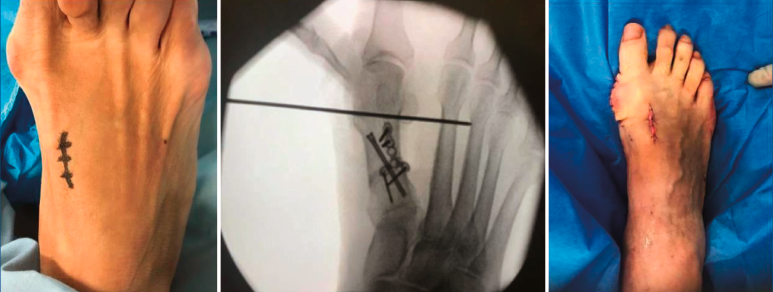

Figura 3. Detalles quirúrgicos de la osteotomía de cierre lateral.

No se objetivó ningún caso de metatarsalgia de transferencia ni de pseudoartrosis. En las Figuras 2 y 3 se pueden ver detalles quirúrgicos de las osteotomías de apertura y cierre.